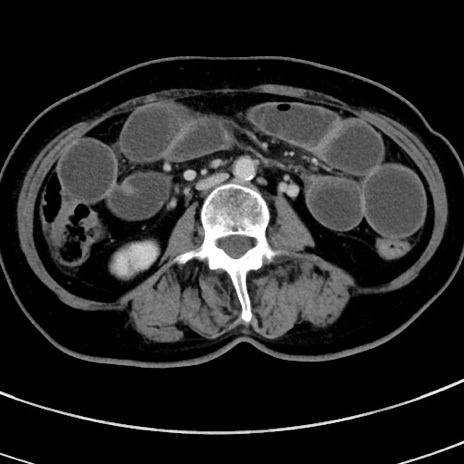

冠状断像

【症例】 60歳代女性

【主訴】むかつき、みぞおちの痛み

【現病歴】3日前よりむかつきがあり、食事がとれない。

【既往歴】糖尿病

【身体所見】発熱なし、心窩部圧痛軽度あるも、腹膜刺激症状なし。

【データ】WBC 7400、CRP 1.92